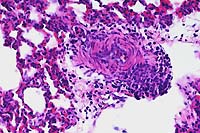

- Case 16-2. Lung. The pulmonary arteriole (20x view)

is expanded by lymphocytes and plasma cells. The endothelium

(both views) is lined by piled up, hypertrophic, endothelial

cells which rarely bear smudgy amphophilic intranuclear inclusions

(arrow head).

- AFIP Diagnosis: Lung: Endothelial degeneration and

hypertrophy, diffuse, with multifocal vasculitis, interstitial

pneumonia, diffuse edema, and endothelial intranuclear inclusion

bodies, black-tailed deer (Odocoileus hemionus columbianus),

cervid.

- In the tissue section of this experimentally infected animal,

the pulmonary parenchyma is multifocally atelectatic, and the

interlobular septa and subpleural spaces are moderately to severely

expanded by edema and very mild inflammation (lymphocytes, plasma

cells, and neutrophils). Small to medium-sized arterioles throughout

the tissue are lined by endothelium in which the nuclei are prominent

and rounded, are darkly basophilic, bulge into the vascular lumina,

and contain darkly amphophilic viral inclusion bodies. Many of

these arterioles contain sloughed luminal endothelial cells admixed

with moderate numbers of mononuclear and polymorphonuclear cells,

and in some of the arterioles, inflammation extends into the

vessel wall where it is admixed with rare, brightly eosinophilic

hyalinized material (fibrinoid necrosis). Throughout the remaining

parenchyma there is multifocal atelectasis, alveolar capillaries

are expanded by neutrophils, and there is expansion of alveolar

septa by moderate numbers of neutrophils and lymphocytes. Transmission

electron microscopy demonstrated endothelial cell necrosis in

the lungs and alimentary tract and adenovirus particles in the

nuclei with protein crystalline arrays.